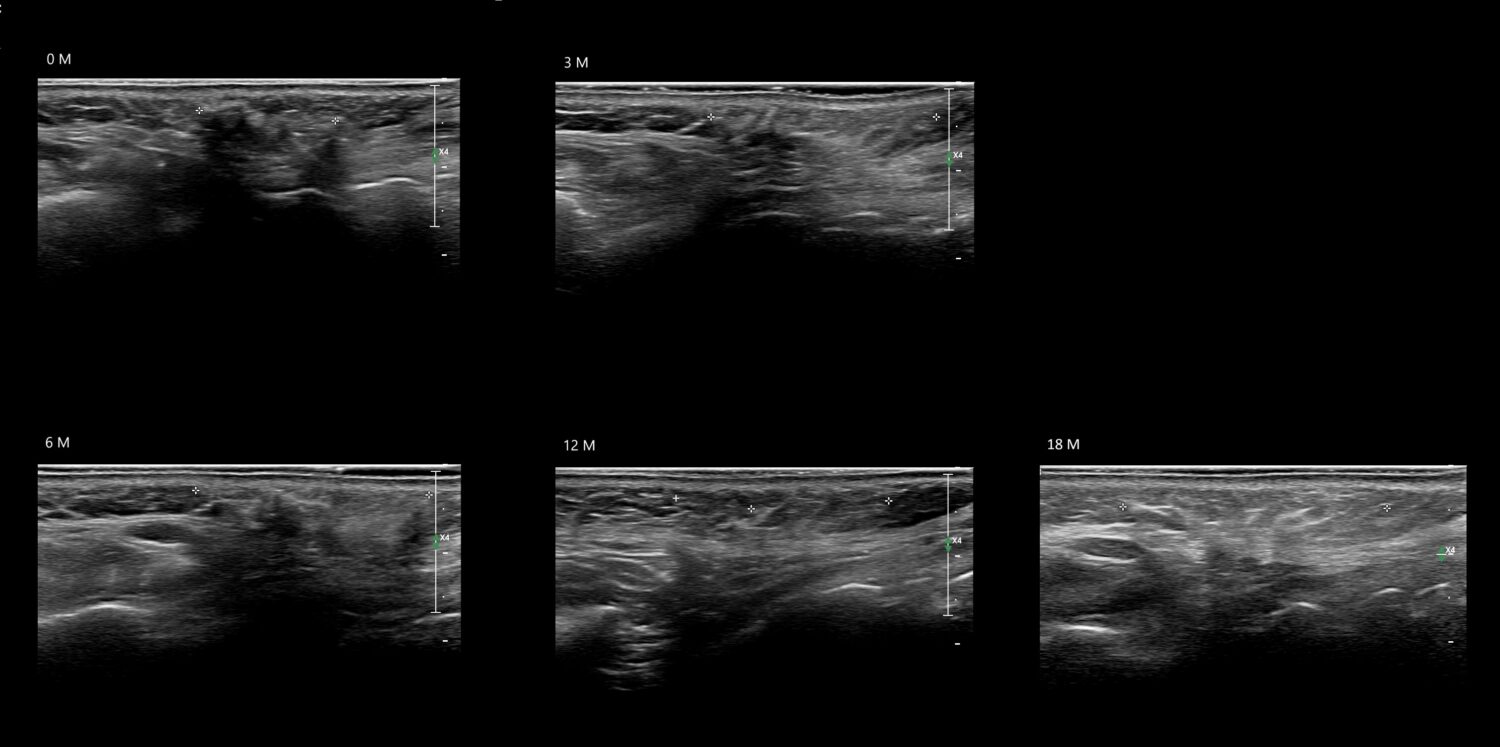

Fillers

Draw in the image on the right where the fillers are located. To check if your answer is correct, please click on the secondary image.